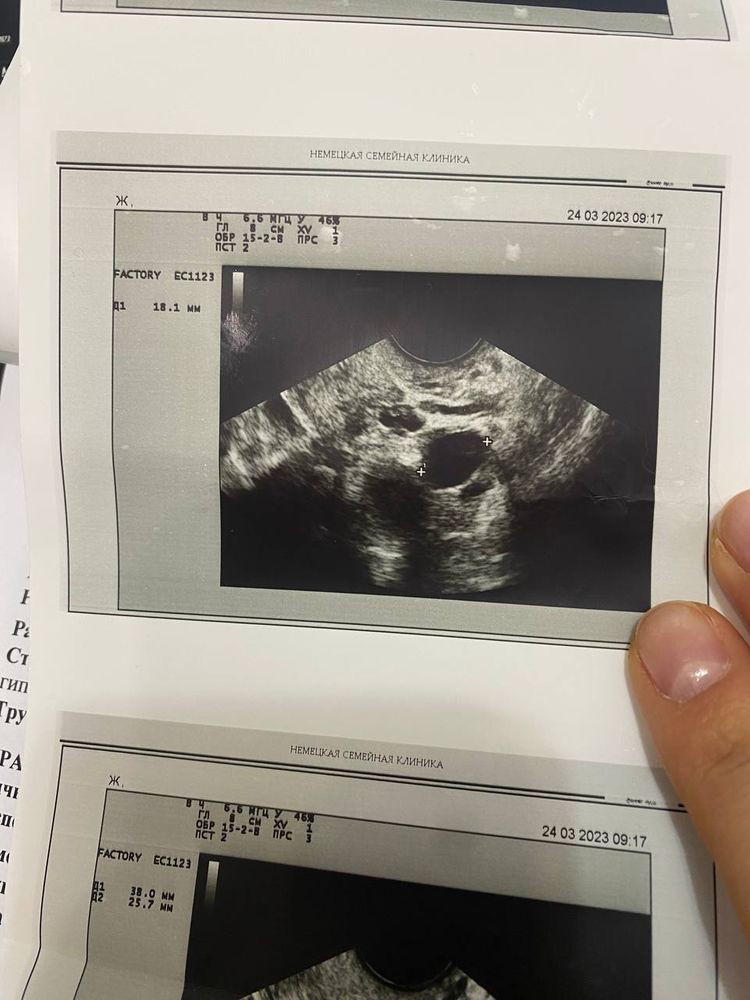

Похоже на доминантный фолликул. У него контуры чётче, чем у жёлтого тела.

Анна, да в том то и дело, что в одной клинике сказали ЖТ, а в другой, что это ДФ, вот и гадаю на кофейной гуще. Я просто ЖТ на узи не привыкла видеть вообще, не отличаю сама.

Екатерина, ну У вас во вторник был 21 , значит вот вот овуляция.. либо в пятницу этот дф сдулся и подумали, что это жт.. либо все таки была овуляция и увидели жт в пятницу как надо… а сегодня возможно второй дф растет, но жт не увидели,то тоже странно.. возможно да, у вас был дф, он рос и сейчас сдувается, пошёл в регрес и не лопнул

Больше похоже на ДФ. А эндометрий пролиферативный или секреторный? По анализу на прогик все будет понятно

Это в пятницу Изображение а это сегодня Изображение

Екатерина, сегодняшний эндик секреторный, эхогенный. Значит и прогик быть должен